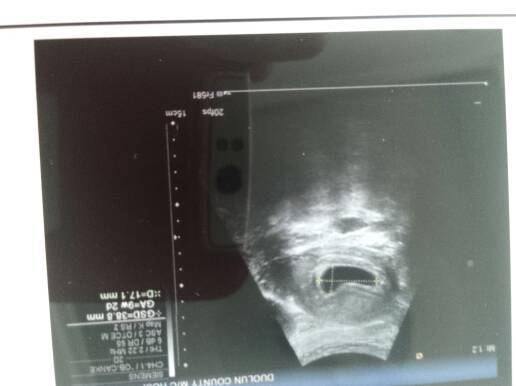

我怀孕今天50天,b超检查妊娠囊3.9*1.7 cm,未见胎囊,正常吗? 我怀孕今天50天,b超检查妊娠囊3.9*1.7 cm,未见胎囊,正常吗? 点击展开 『嗳已成咴 ~ 2014-07-18 11:38 为您推荐: 其他回答 哦 坚持就是胜訓利 2014-07-18 12:07 两个月了月经会推迟的。怎么办 坚持就是胜訓利 2014-07-18 12:07 一个礼拜看 坚持就是胜訓利 2014-07-18 12:06 我现在也是。快两个月了还没有 坚持就是胜訓利 2014-07-18 12:05 嗯。到那时再晚的也能看出来胎心。祝你好孕 哲哲宝宝👄 2014-07-18 11:44 加载更多 相关问题 已怀孕八8周加3天,今天b超了显示妊娠囊大小约15x9cm,未见卵黄囊及胚芽,医生说我的胎儿只有5 怀孕第5周零3天,这是血检报告,请问是好吗?怎么孕酮那么高?今天有朋友查宫角妊娠,我要怎么避免出现 在线医生,帮帮忙,怀孕40天,今天做了B超说,宫腔上段可见一大小约13x7mm液暗区,这正常吗?